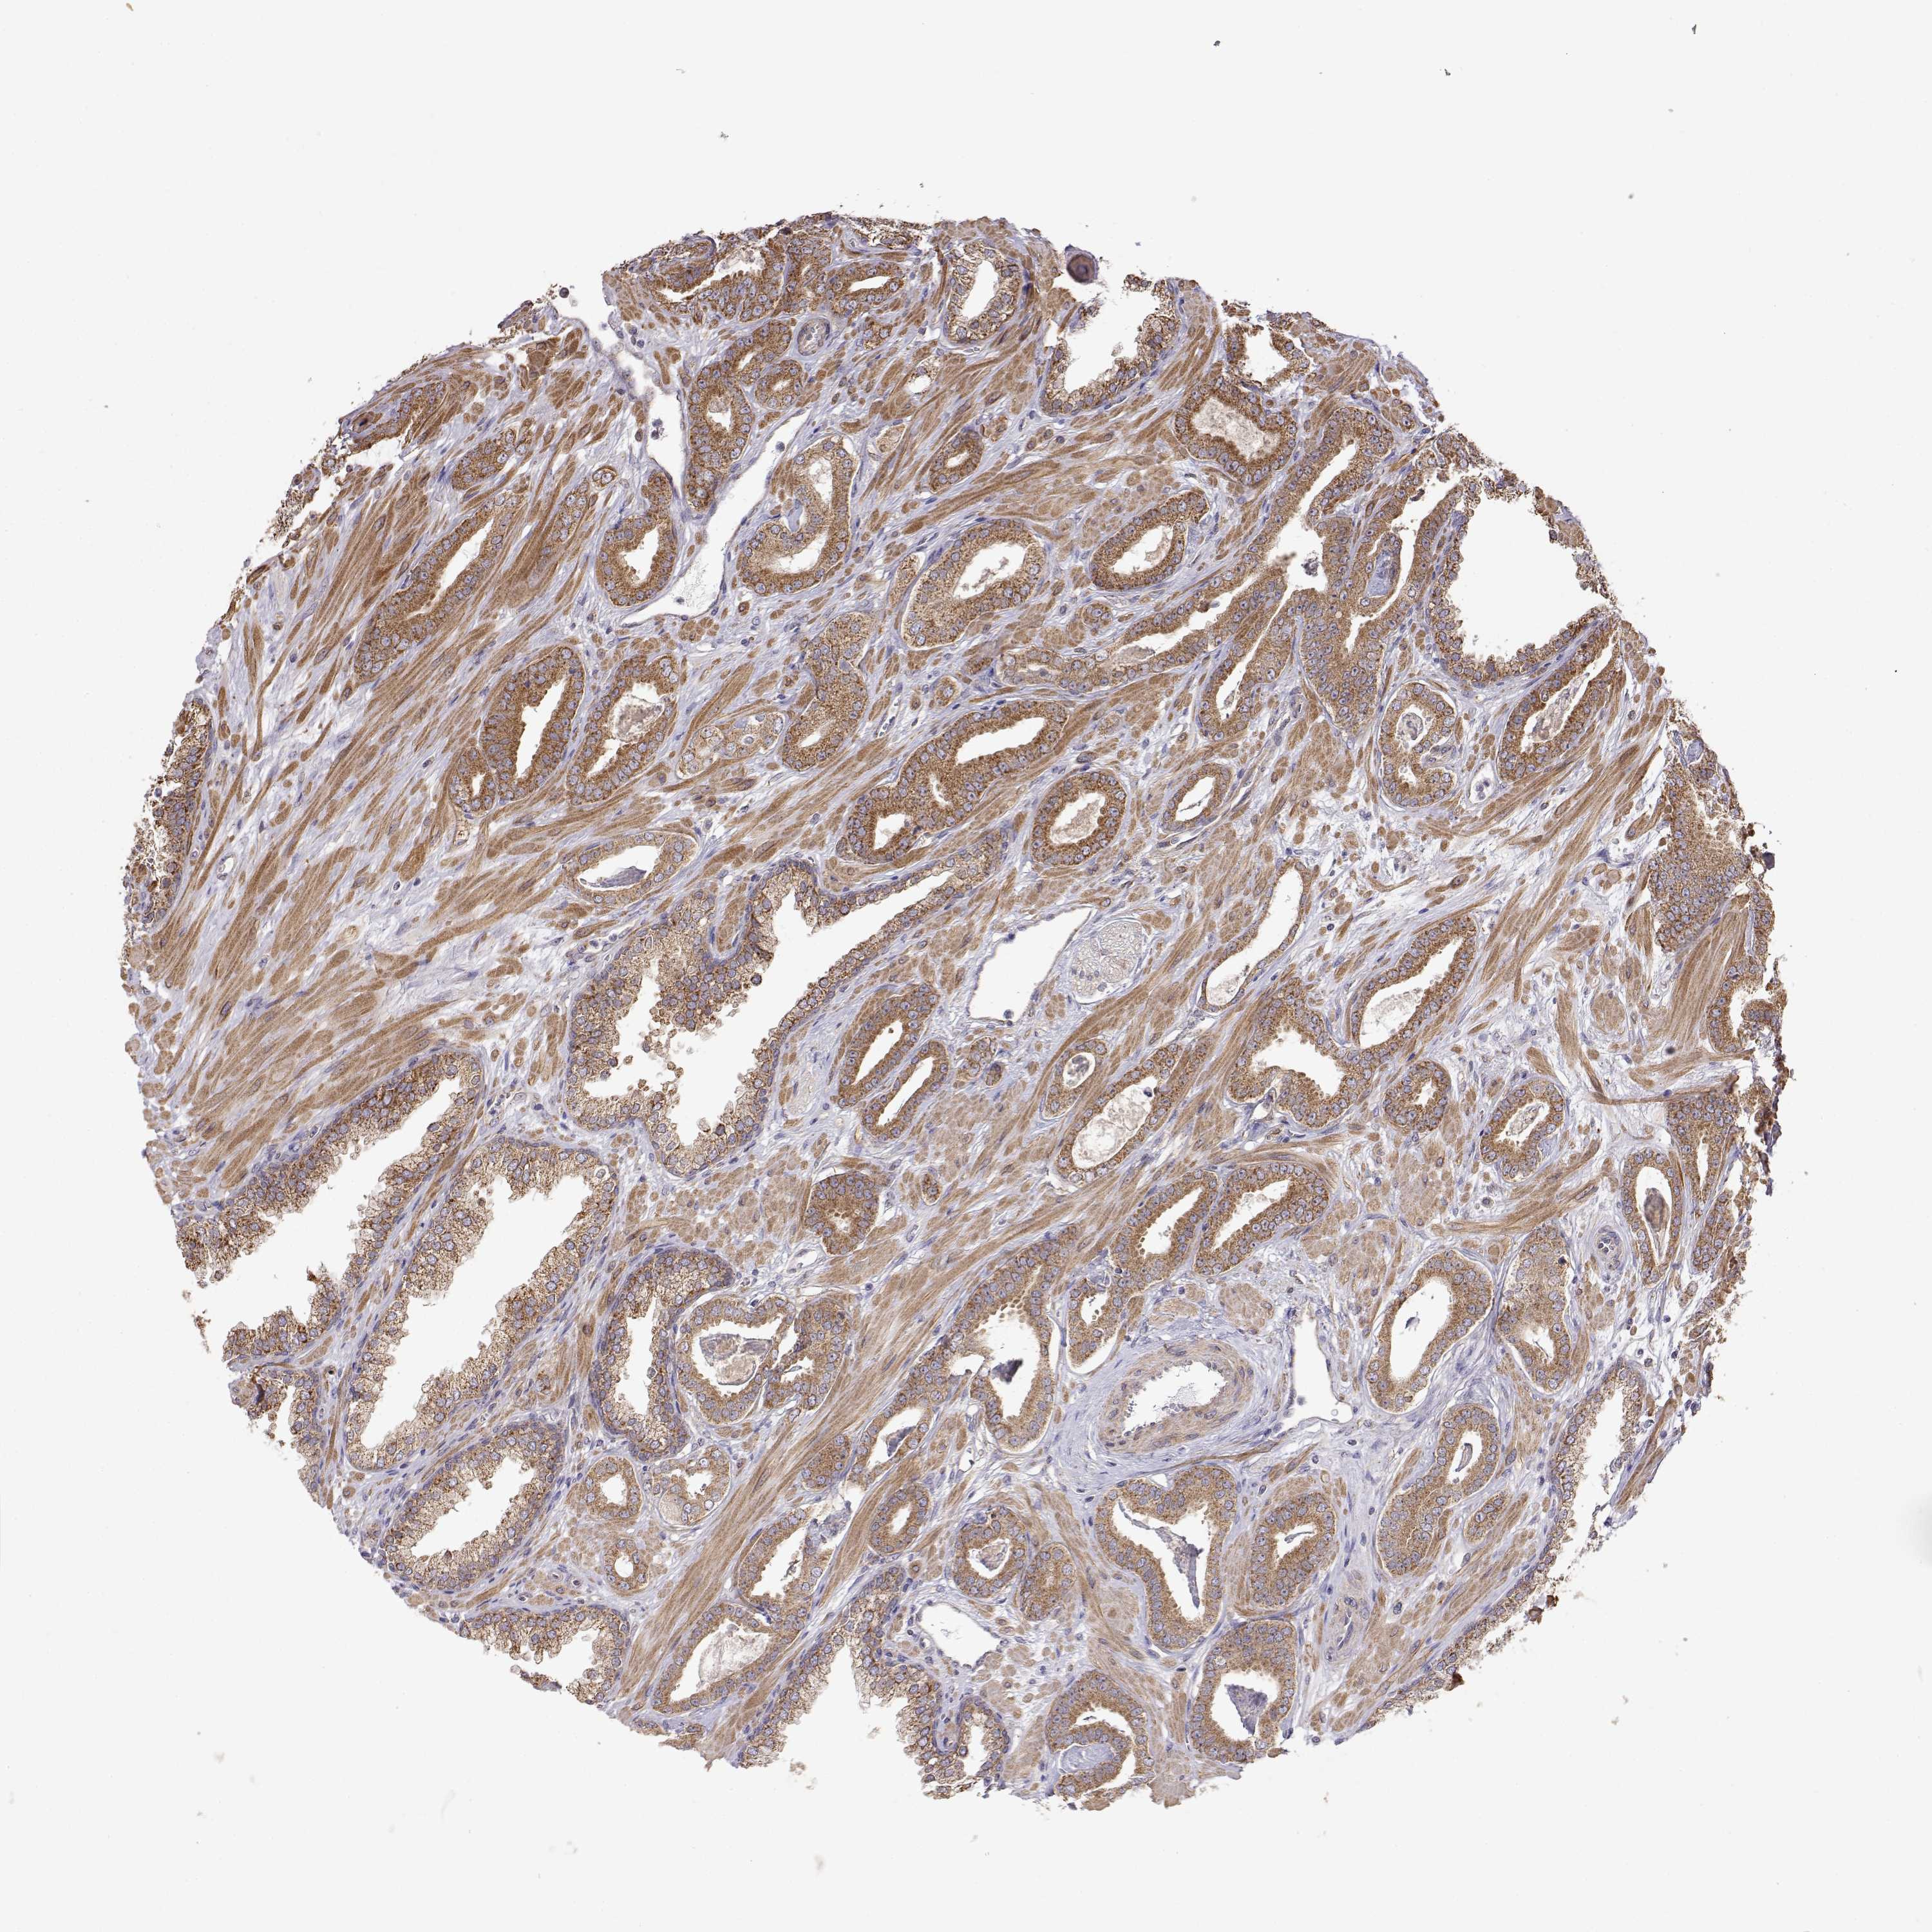

PROSTATE CANCER - Protein expressioni

A mouse-over function shows sample information and annotation data. Click on an image to view it in a full screen mode. Samples can be filtered based on level of antibody staining by selecting one or several of the following categories: high, medium, low and not detected. The assay and annotation is described here.

Note that samples used for immunohistochemistry by the Human Protein Atlas do not correspond to samples in the TCGA dataset.

Antibody stainingi

Antibody staining in the annotated cell types in the current human tissue is reported as not detected, low, medium, or high, based on conventional immunohistochemistry profiling in selected tissues. This score is based on the combination of the staining intensity and fraction of stained cells.

Each image is clickable and will lead to virtual microscopy that enables deeper exploration of all samples and also displays staining intensity scores, fraction scores and subcellular localization as well as patient and tissue information for each sample.

Antibody HPA073653

Staining

High

Medium

Low

Not detected

Intensity

Strong

Moderate

Weak

Negative

Quantity

>75%

75%-25%

<25%

None

Location

Nuclear

Cytoplasmic/membranous

Cytoplasmic/membranous,nuclear

Adenocarcinoma, High grade

Adenocarcinoma, NOS

Adenocarcinoma, Low grade